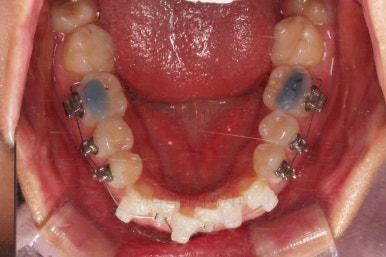

교정 시작 9개월만인데요.

벌써 치열이 가지런해졌네요.

입 안의 모습만 보면 조만간 마무리가 가능할 정도로 많은 부분들이 좋아졌는데요.

교정이라는게 단순한 교합/입 안만 보는 것이 아니라 얼굴모습과의 조화, 얼굴모습의 개선까지도 생각해야 되므로 추가적인 고려사항이 많았습니다.